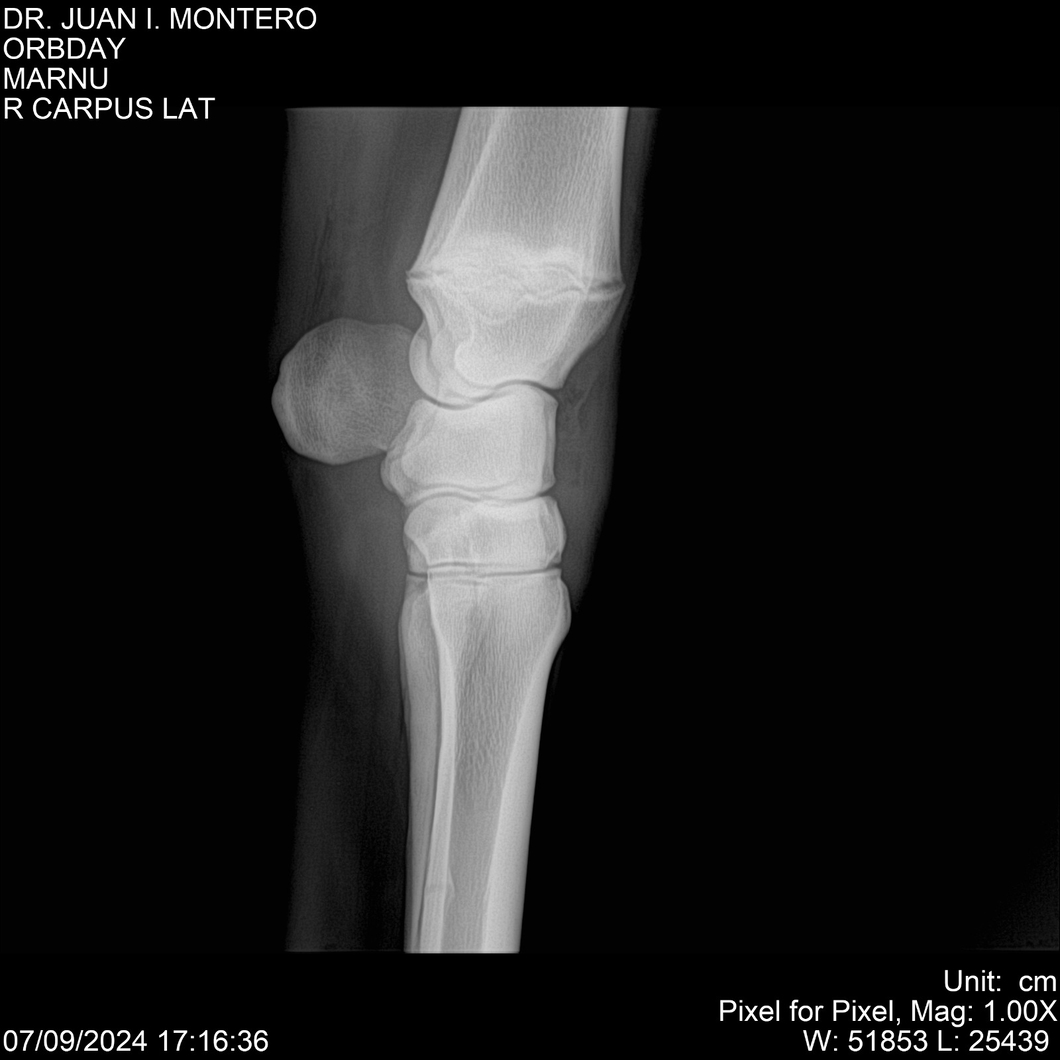

Visualizaciones